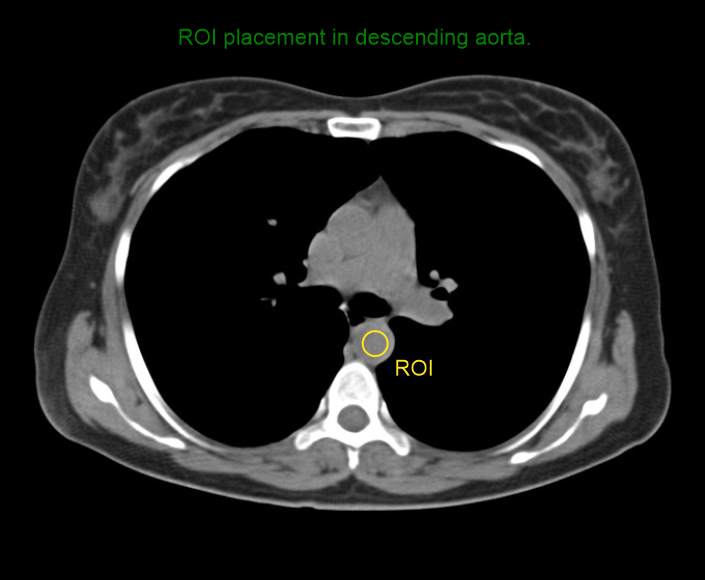

- Place triggering region of interest (ROI) in the descending aorta.

- Program the threshold value to 160 HU.

- Set S & V initiation delay to 10 seconds.

- Place zero delay time for arterial scan.